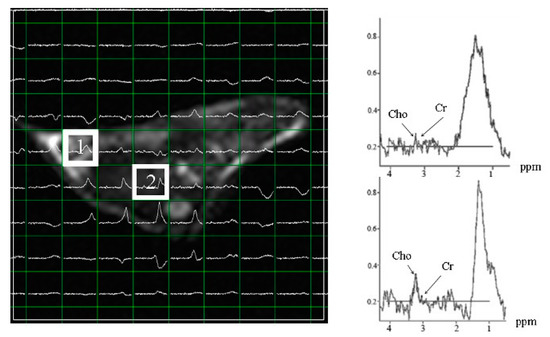

Subcutaneous Hep-G2- and Huh 7-xenografted mice were examined for multi-voxel hepatoma spectra at 25 days post-inoculation (Figure 6A,C). Hep-G2 xenografts showed the maximum level of choline/creatine at a different site from the inoculation point (Figure 6B), whereas the maximum choline/creatine level was observed near the inoculation point in Huh 7 xenografts (Figure 6D). These results suggest a greater capability of Hep-G2 cells to metastasize than that of Huh 7 cells.

Figure 6.

Multi voxel spectra of hepatoma in subcutaneous Hep-G2- (A,B) and Huh 7- (C,D) xenografted mice at 25 days post-inoculation. (A) The choline/creatine level at the inoculated point in (B). (C) The choline/creatine level at the inoculation point in (D). The maximum choline/creatine level was detected at some distance from the inoculation point in Hep-G2-xenografted mice. The maximum choline/creatine level was near the inoculation point in Huh 7-xenografted mice. Circles indicate the point of inoculation.

Xenografted mice derived from two hepatoma cell lines showed minimal choline/creatine levels at the time of inoculation compared to those in the vehicle group. However, choline levels were higher in regions distant from those at the site of inoculation (Table 3), indicating that the two cancer cell lines metastasized to other parts after approximately 5–25 days of inoculation. Further, tagitinin C treatment (15 g/mouse/day) for 15–25 days reduced the tumorigenicity of xenografts derived from the two cell lines.